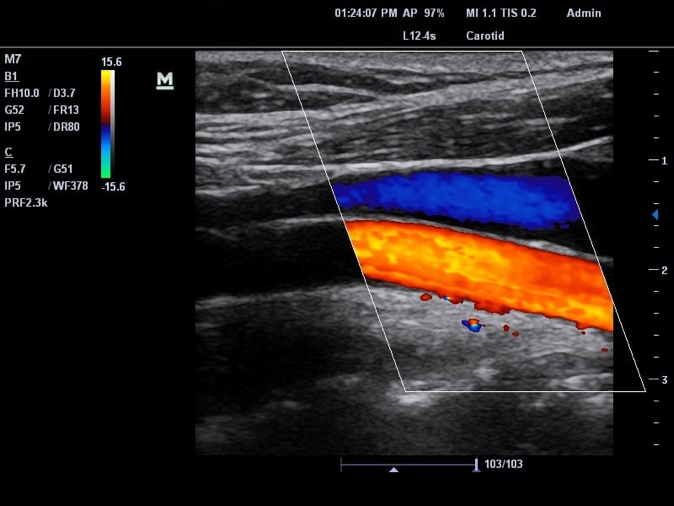

Siêu âm Dopplẻ hệ động mạch cảnh:

Sàng lọc tình trạng bệnh nhân tắc nghẽn hoặc hẹp động mạch cảnh.

Hình 7. Siêu âm Doppler hệ động mạch cảnh

Siêu âm Doppler mạch máu:

Khảo sát : ĐM cảnh – sống đoạn ngoài sọ, động tĩnh mạch chi trên, chi dưới, ĐM chủ bụng, các ĐM nuôi các tạng trong ổ bụng, ĐM thận, mạch máu não

Hình 8. Siêu âm Doppler mạch máu